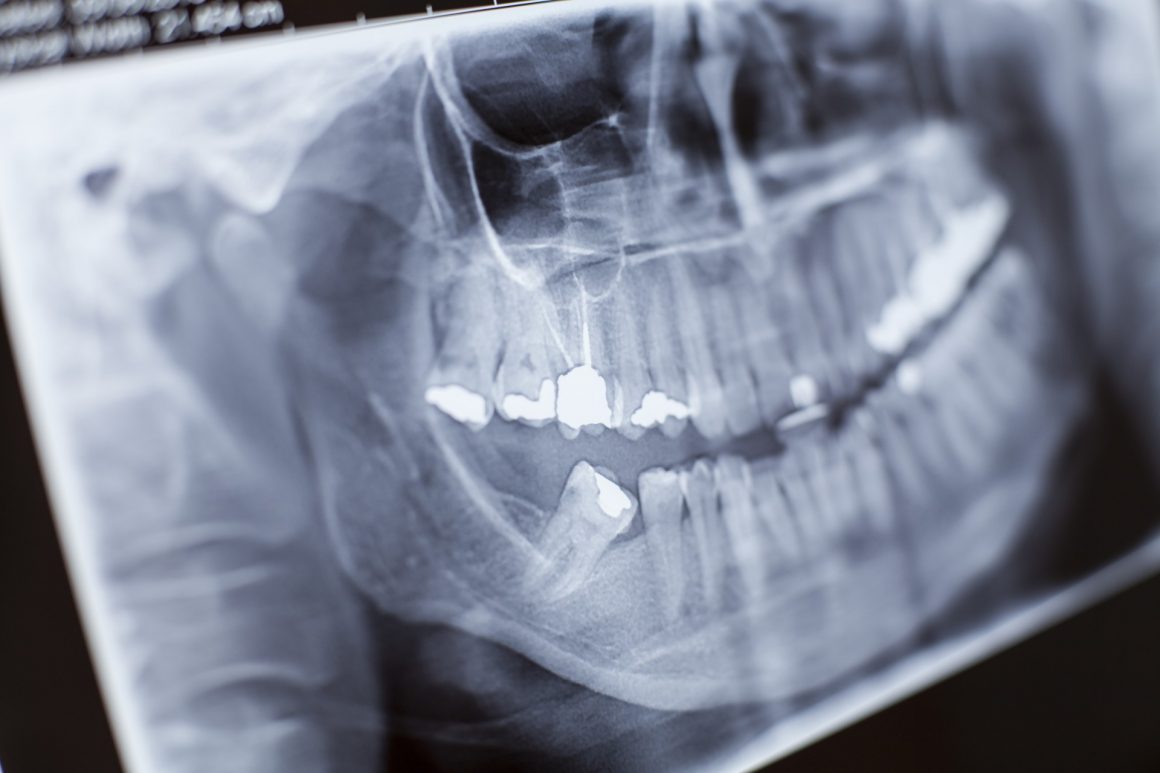

Dr. Benham’s office is equipped with state-of-the-art X-ray technology, allowing us to identify & diagnose potential dental problems. Visit the the ADA’s Mouth Healthy Website to learn more about X-rays. Services detailsLikes:2 Author:adminDate:August 8, 2017June 2, 2020Categories:Services